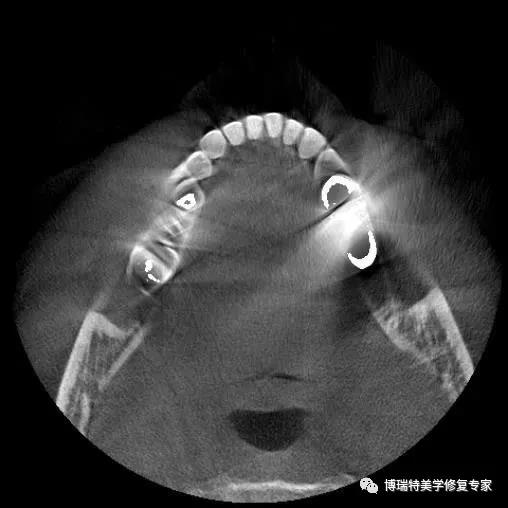

智能3D全景CBCT 多金属去伪影图

普通CBCT 多金属去伪影图(同一患者)

上颌窦底,骨小梁与下颌神经管清晰可见

植体周围无阴影,植体螺纹清晰可见